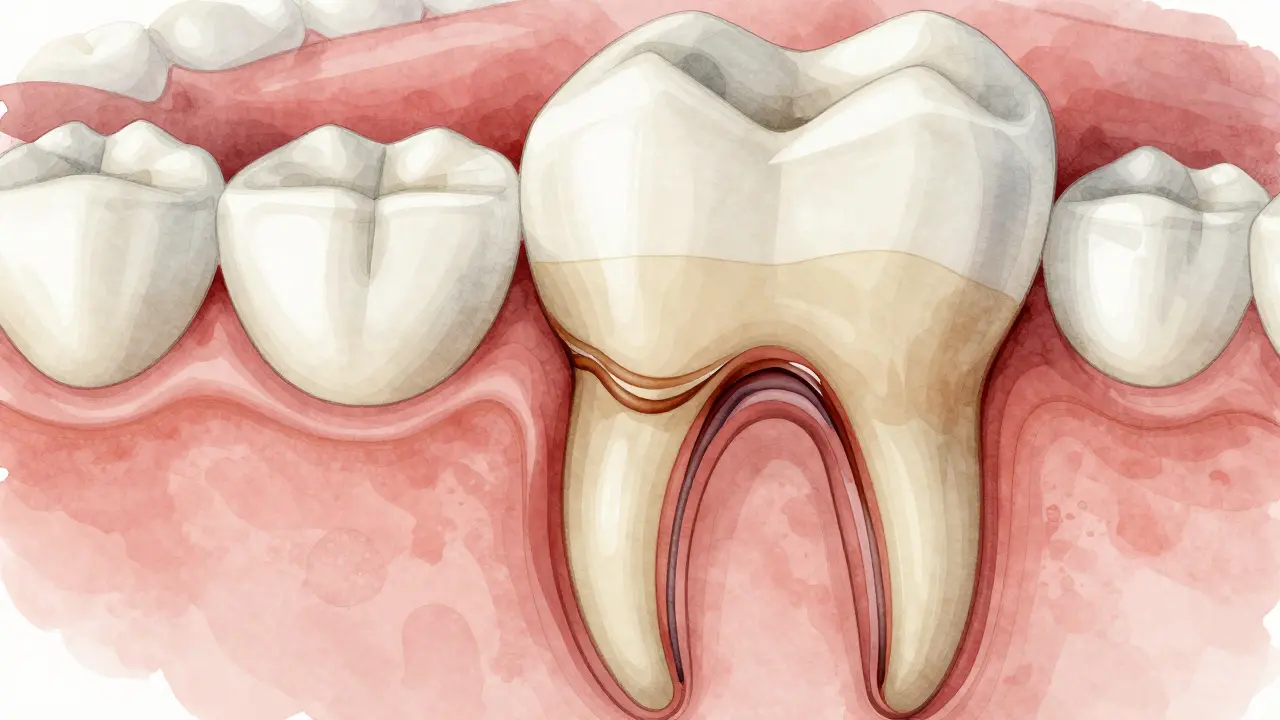

Příčný řez zubu s kazem pod plombou, šířícím se do dentinu.

Když se kaz nezachytí včas, začne se šířit hlouběji. Nejprve prožírá sklovinku, pak dentin - a ten je měkký a citlivý. V tomto stádiu začne být zub citlivý na studené, teplé nebo sladké. Pokud se to nezastaví, kaz dorazí k zubnímu nervu. Pak nastane bolest - často silná, noční, která se nechce odejít. A teprve teď se musí dělat kořenová léčba nebo zub vytrhávat.